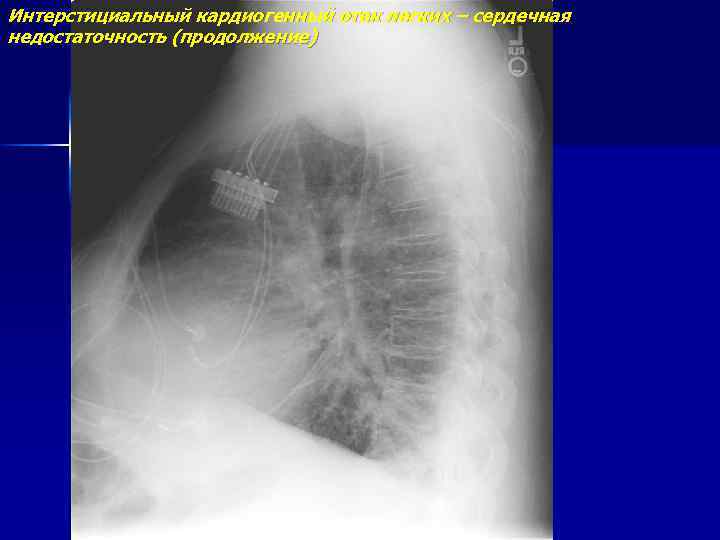

Интерстициальный кардиогенный отек легких – сердечная недостаточность (продолжение)